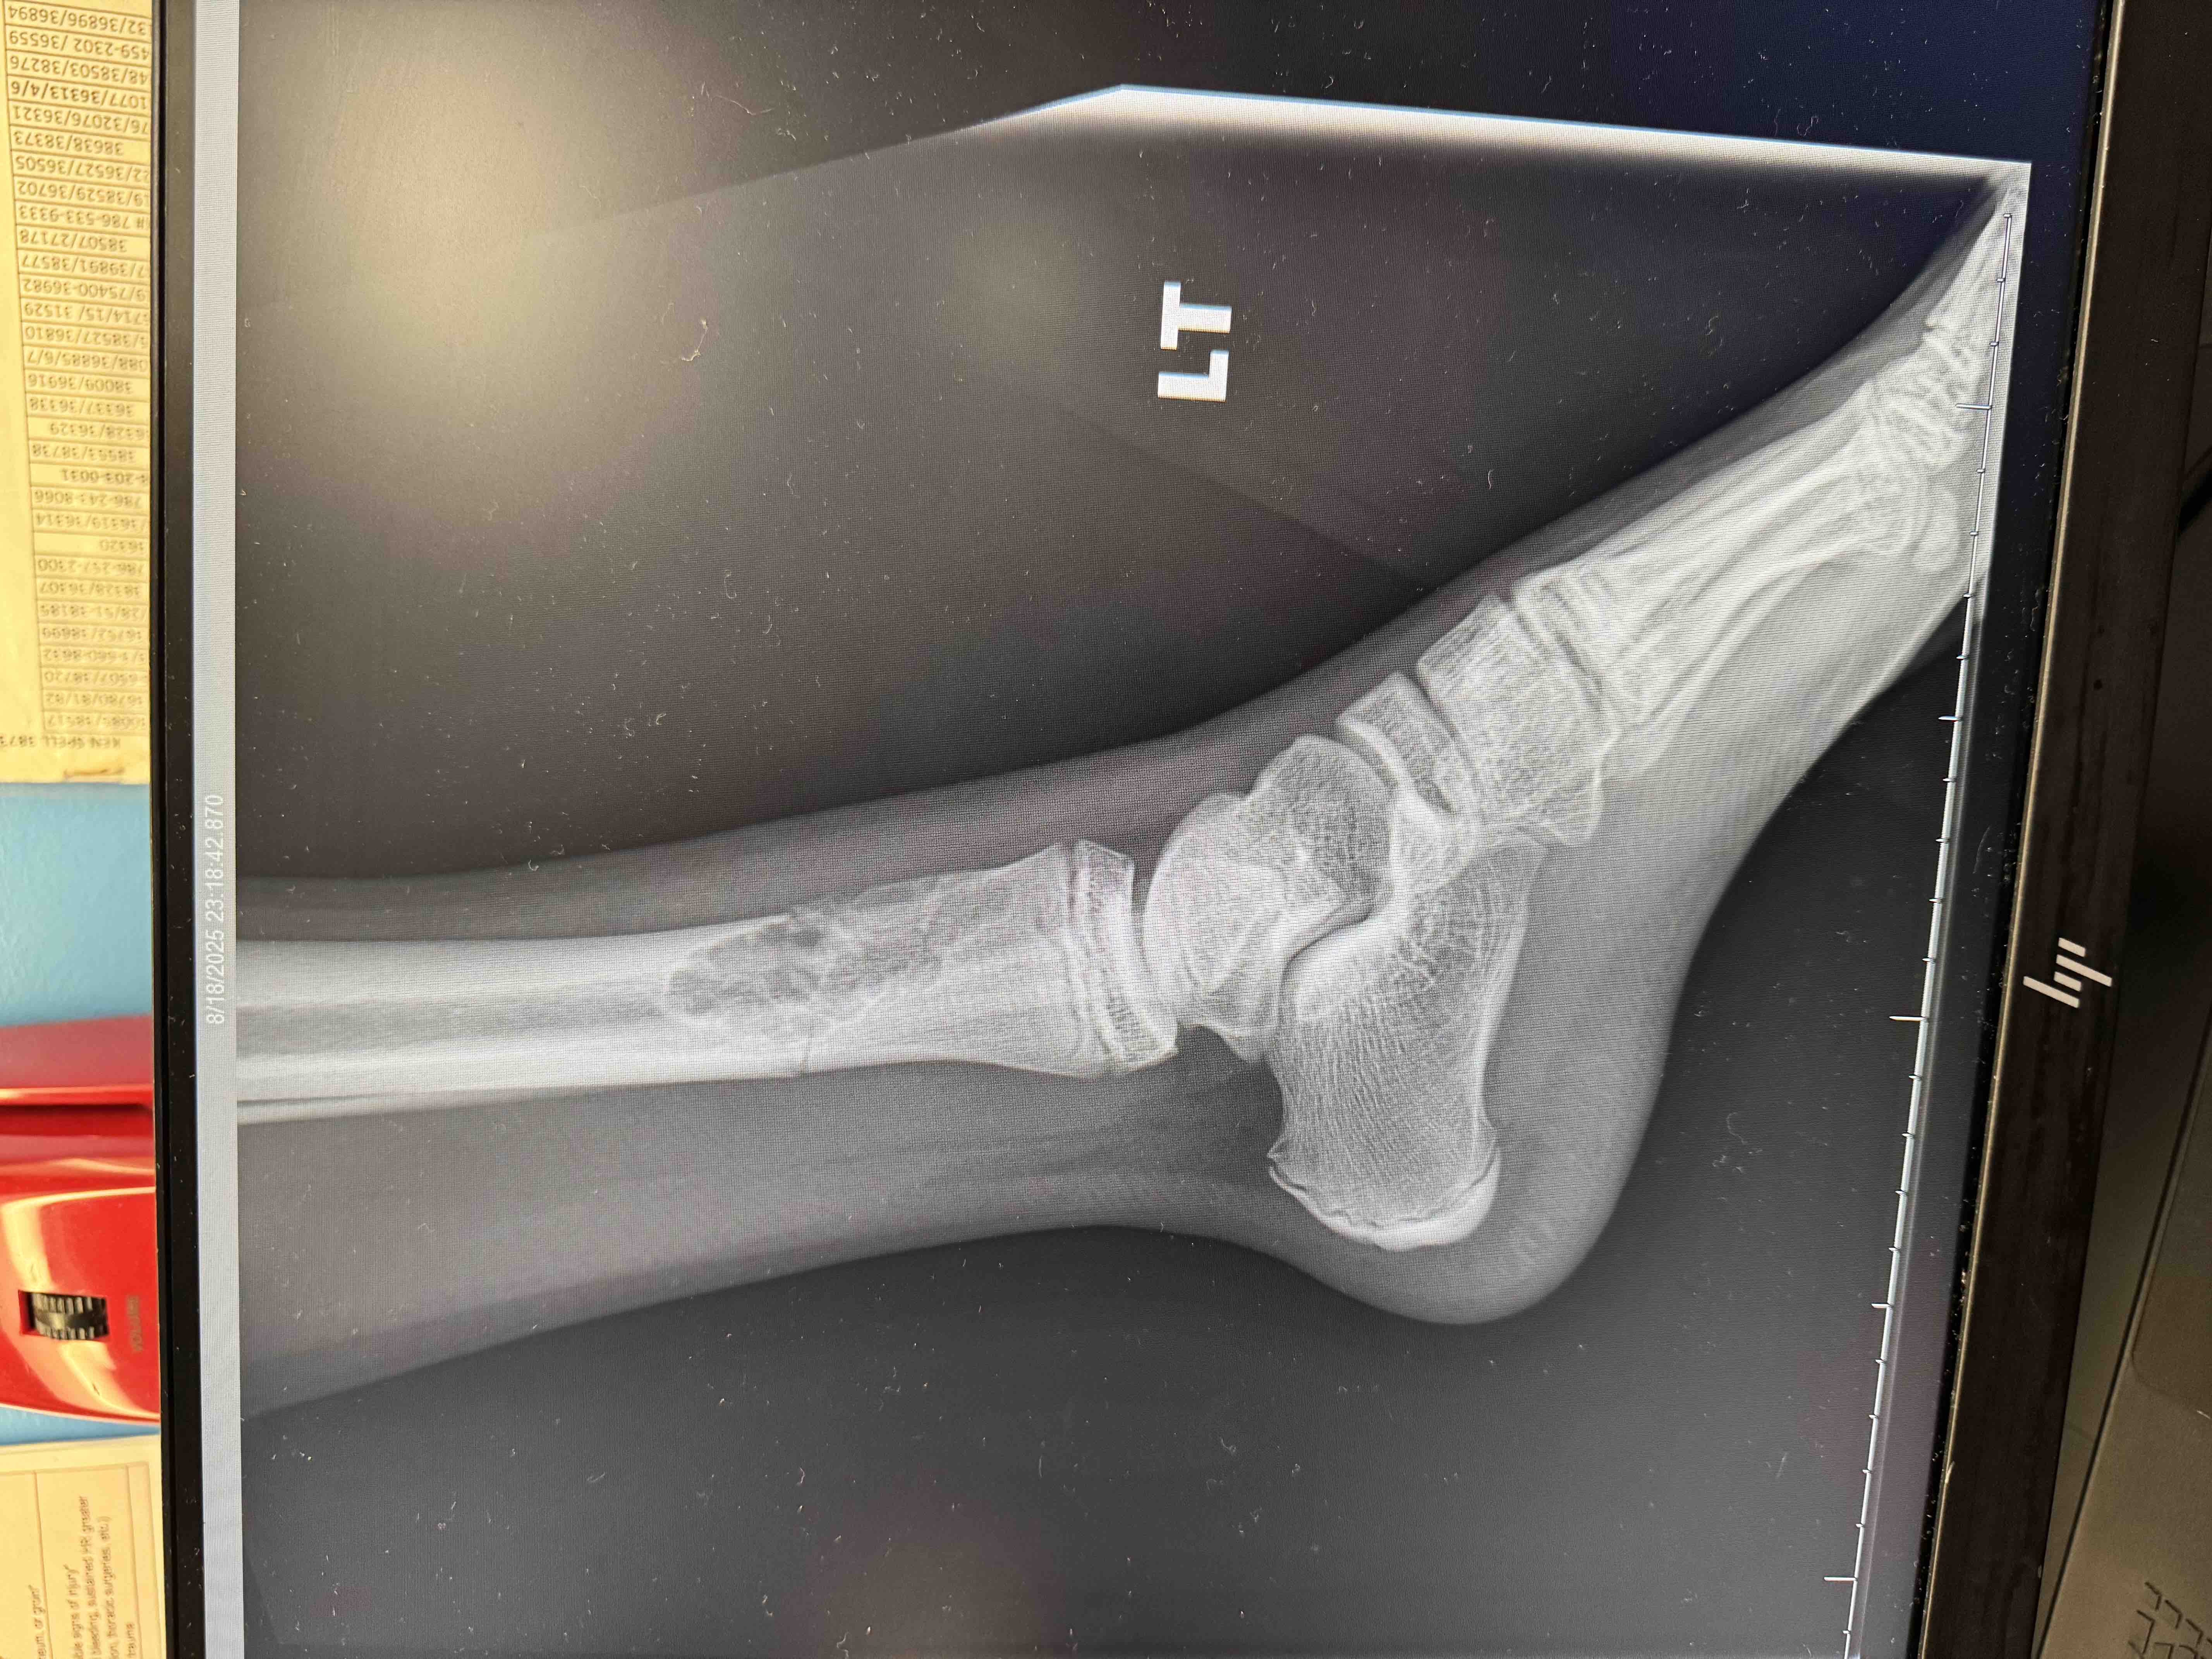

In August of last year, my son Agustín fractured his femur while playing soccer — the sport he loves and a big part of his dreams and goals. What initially seemed like a simple fracture led to the discovery of something more serious: an Aneurysmal Bone Cyst, a bone tumor that has been growing and weakening his bone.

Since then, we have endured months of medical tests, constant monitoring, casts, immobilization, and uncertainty. Recent imaging showed that the tumor has grown, and we are now awaiting a biopsy to confirm that it is completely benign, as doctors strongly believe. With faith, we hope the results will fully rule out cancer so we can proceed with the surgery that is currently scheduled.

En agosto del año pasado, mi hijo Agustín se fracturó el fémur mientras jugaba fútbol, el deporte que ama y que forma parte de sus sueños y metas. Lo que comenzó como una fractura terminó revelando algo más complejo: un Aneurysmal Bone Cyst, un tumor óseo que ha venido creciendo y debilitando su hueso.

Desde entonces, hemos pasado meses de estudios, controles constantes, yesos, inmovilizaciones y mucha incertidumbre. Recientemente, los exámenes mostraron que el tumor ha crecido, y ahora estamos esperando una biopsia para confirmar que sea completamente benigno, como los médicos sospechan. Con fe, esperamos que el resultado descarte cualquier posibilidad de cáncer y que podamos proceder con la cirugía ya programada.